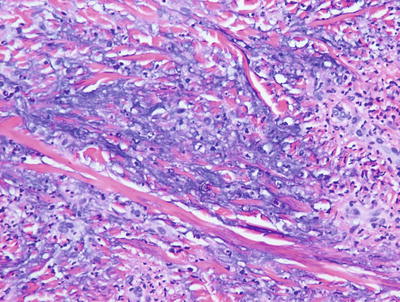

6.7.2 Histology

Palisaded neutrophilic and granulomatous dermatitis is often associated with collagen vascular diseases [71]. The histologic features include leukocytoclastic vasculitis associated with foci of collagenous degeneration in early lesions (Figs. 6.24 and 6.25). As lesions become more fully developed, areas of leukocytoclasis with fibrin deposition and degenerated collagen are found in the centers of palisading histiocytes (Fig. 6.26). Later lesions have fibrosis, minimal neutrophilic debris, and less cellularity.

Fig. 6.24

A diffuse infiltrate of histiocytes and neutrophils is seen throughout the dermis in palisaded neutrophilic and granulomatous dermatitis

Fig. 6.25

There is abundant interstitial mucin admixed with neutrophils and karyorrhectic debris in palisaded neutrophilic and granulomatous dermatitis